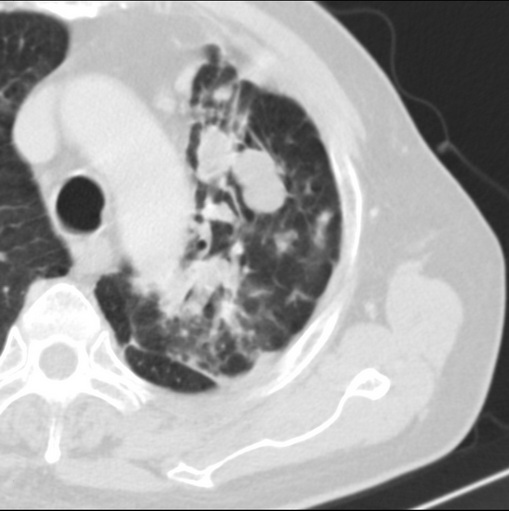

男性患者 81岁 咳嗽 咳痰 咯血

强化较典型,左上肺癌并纵膈淋巴结转移;左上肺结核并空洞形成;胸膜增厚.

变态反应性支气管肺曲霉菌病与鳞癌鉴别,前者可能性大,左侧胸膜肥厚。

标题: 考虑左侧中央型肺癌可能性大

肿块贴近左肺门,包绕左上肺动脉,形态不规则。肿块增强扫描中度强化。纵膈内主动脉弓左旁间隙、气管隆突前、下间隙见多枚淋巴结影。综上考虑左侧中央型肺癌可能性大。图片没有完整上传,尤其是左肺上叶支气管分支层面没有上传,因此不好判断是叶支气管中断还是段支气管中断。另外,下图红色部分所示是“黏液支气管征”吗?